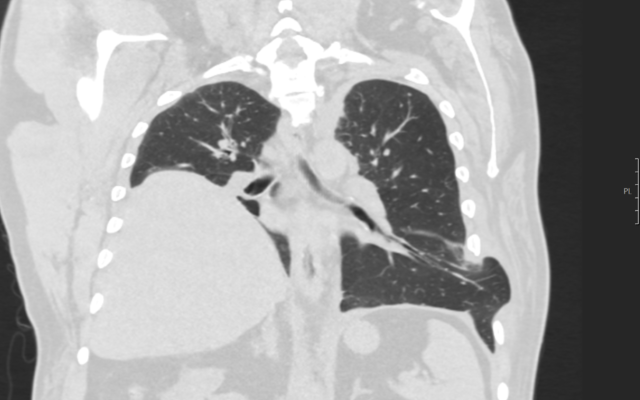

Een 66-jarige man kwam bij de huisarts met een sinds enkele dagen bestaande hoest. Hij was bekend met diabetes mellitus type 2, hypertensie en een bij toeval ontdekte hoogstand van de rechter diagfragmahelft met onbekende oorzaak. Omdat er op dat moment geen afwijkingen waren bij lichamelijk onderzoek, werd afgesproken om af te wachten.

Twee dagen later meldde de patiënt zich weer bij de huisarts. Na een stevige hoestbui was er pijn en een hematoom ontstaan in de linker flank (figuur a). Hij gebruikte geen antistolling. Het hematoom werd geduid als passend bij een gesprongen bloedvat. Gezien de klinisch stabiele…